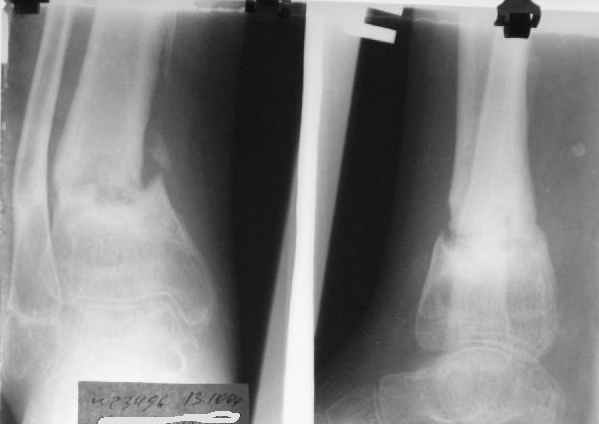

Ребенок 12 лет, поступил после падения с высоты примерно 2,5м.

Перелом костей н\3 правой голени со смещением. Перелом большеберцовой кости можно охарактеризовать как компрессионно-оскольчатый.

Скелетное вытяжение за пяточную кость.

В первые сутки значительный отек с\3, н\3голени, стопы с развитием практически неуловимого в нашей стране ;) компартмент синдрома (фасциотомии не проводилось), недочеты по укладке на скелетном

вытяжении.

Формирование некроза кожи по задней поверхности н\3 голени~ 1 %, вторичное заживление, кожная пластика. Нейропатия м\берцового нерва (отсутствие активного разгибания 1 пальца) На вытяжении около 8 нед, в дальнейшем в гипсовых повязках ~ 8 мес.

В январе 2005: варусная деформация н\3 голени, болевой с-м, комбинированная контрактура г\стопного сустава, нейропатия м\берцового нерва сохраняется слабость разгибания 1 пальца.

Операции: 1 Клиновидная резекция на вершине деформации м\берцовой кости.

2 Тугоподвижный ложный сустав н\3 б\берцовой кости. Рубцы выполняющие пространство между отломками, канал проксимального отломка иссечены.

Одномоментное устранение деформации, остеосинтез Г-образной пластиной.

Пластика по Хахутову.

Заживление проксимальной части раны вторичным натяжением без нагноения. Рана зажила. Спицы удалены через 1,5 недели после операции.

Особого смысла в них не было.

Учитывая фон (интеллект, etc) гипсовая повязка.

На данный момент ходит при помощи костыля (без присмотра -без костыля :), разрабатывает движения в г\стопном суставе.